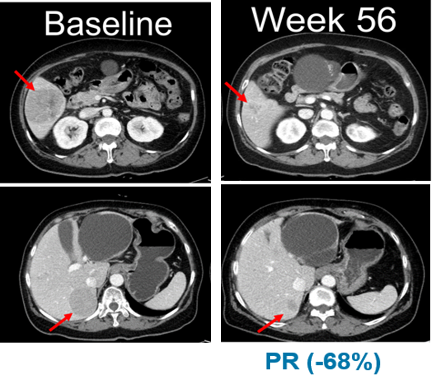

적응증 확장 임상의 NRAS 변이 흑색종 연구에서는 13명의 환자 중 5명이 부분반응(PR)을 보였으며 최고반응률(BORR)은 38.5%로 나타났다.

13명의 환자 중 11명은 이전에 면역관문억제제(CPI)를 투여받았다. 회사에 따르면 면역관문억제제 투여 환자군 대상 최고반응률(BORR)은 45.5%로 확인됐다. 무진행생존기간(PFS)의 중간값은 7.3개월이다.